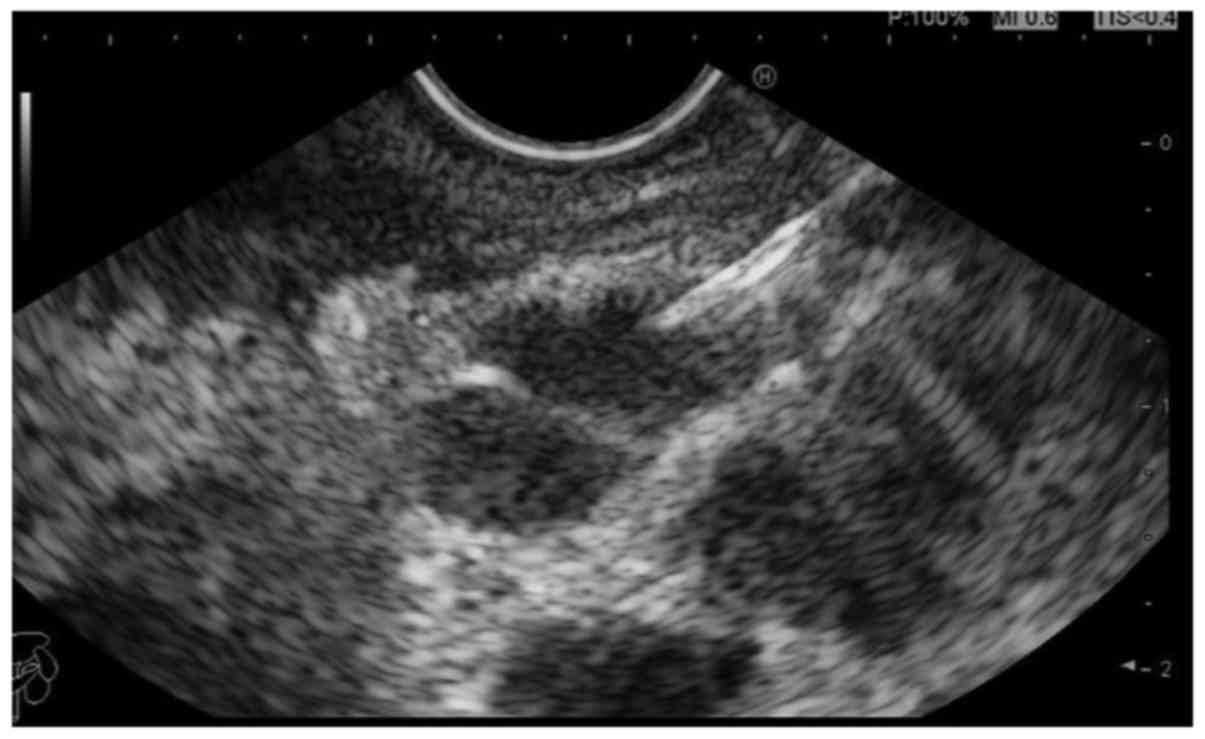

Endoscopic Ultrasound Biopsy. biopsy can determine the presence of cancer and examine its characteristics. What is endoscopic ultrasound used for? The ultrasound can provide an. endoscopic ultrasound (eus) has become an important diagnostic modality for the identification and risk. an ultrasound may be a helpful resource during biopsies and certain procedures. take a sample of tissue (biopsy) that can help diagnose an abnormal area. endoscopic ultrasound (eus) is a procedure that uses sound waves to take pictures of the pancreas, bile duct and digestive tract. endoscopic ultrasound (eus) is a test that uses a camera and sound waves to produce live images of parts of the digestive system. endoscopic ultrasound (eus) is an increasingly available diagnostic and therapeutic tool used within the uk. pdac sampling by traditional tissue biopsy and liquid biopsy techniques. endoscopic ultrasound (eus) is a procedure that examines your gastrointestinal tract. Current diagnostic workup for pdac. endoscopic ultrasonography (eus) is a combination of endoscopy and ultrasonography. Put in a small tube (stent) to open up a blockage. Eus can help diagnose conditions in the upper gi tract (esophagus, stomach and duodenum), the lower gi tract (colon and rectum) and nearby organs including the lungs, pancreas, liver and gallbladder.

pdac sampling by traditional tissue biopsy and liquid biopsy techniques. what is endoscopic ultrasound (eus)? Current diagnostic workup for pdac. The ultrasound can provide an. Eus can help diagnose conditions in the upper gi tract (esophagus, stomach and duodenum), the lower gi tract (colon and rectum) and nearby organs including the lungs, pancreas, liver and gallbladder. This includes organs such as the stomach, pancreas, and gallbladder, as well as nearby structures and tissues like lymph nodes. endoscopic ultrasonography (eus) is a combination of endoscopy and ultrasonography. endoscopic ultrasound (eus) is a procedure that examines your gastrointestinal tract. endoscopic ultrasound (eus) is a test that uses a camera and sound waves to produce live images of parts of the digestive system. our goal is to collect and review the most recent data on the advances in endoscopic ultrasound guided liver.

Endoscopic Ultrasound Biopsy Endoscopic ultrasound (eus) is a procedure to examine the inside of your digestive. endoscopic ultrasound (eus) has become an important diagnostic modality for the identification and risk. Put in a small tube (stent) to open up a blockage. biopsy can determine the presence of cancer and examine its characteristics. This includes organs such as the stomach, pancreas, and gallbladder, as well as nearby structures and tissues like lymph nodes. Endoscopic ultrasound (eus) is a procedure to examine the inside of your digestive. our goal is to collect and review the most recent data on the advances in endoscopic ultrasound guided liver. pdac sampling by traditional tissue biopsy and liquid biopsy techniques. crinò sf, di mitri r, nguyen nq, tarantino i, de nucci g, deprez ph, carrara s, kitano m, shami vm, fernández. an ultrasound may be a helpful resource during biopsies and certain procedures. endoscopic ultrasound (eus), developed in the 1980s, was initially predominantly used for guidance of fine. take a sample of tissue (biopsy) that can help diagnose an abnormal area. endoscopic ultrasound (eus) is a procedure that examines your gastrointestinal tract. The ultrasound can provide an. endoscopic ultrasound (eus) is a procedure that uses sound waves to take pictures of the pancreas, bile duct and digestive tract. endoscopic ultrasonography (eus) is a combination of endoscopy and ultrasonography.